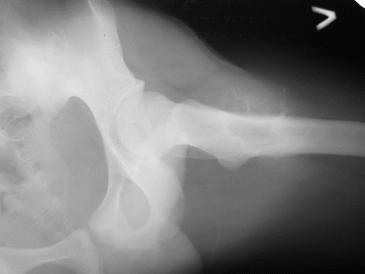

Здравствуйте ,уважаемые коллеги.Обратился парень 15ти лет с жалобами на боли в левом

коленном суставе. При обследовании обнаружена опухоль в в/з левой бедренной кости.

Проведено КТ заключение( остеохондрома) Подскажите пожалуйста, стоит ли сделать биопсию

перед операцией .Кокой операционный доступ и технику операции Вы посоветуете. С уважением

Игорь.

Имя     : IMG_1695tumor.jpg